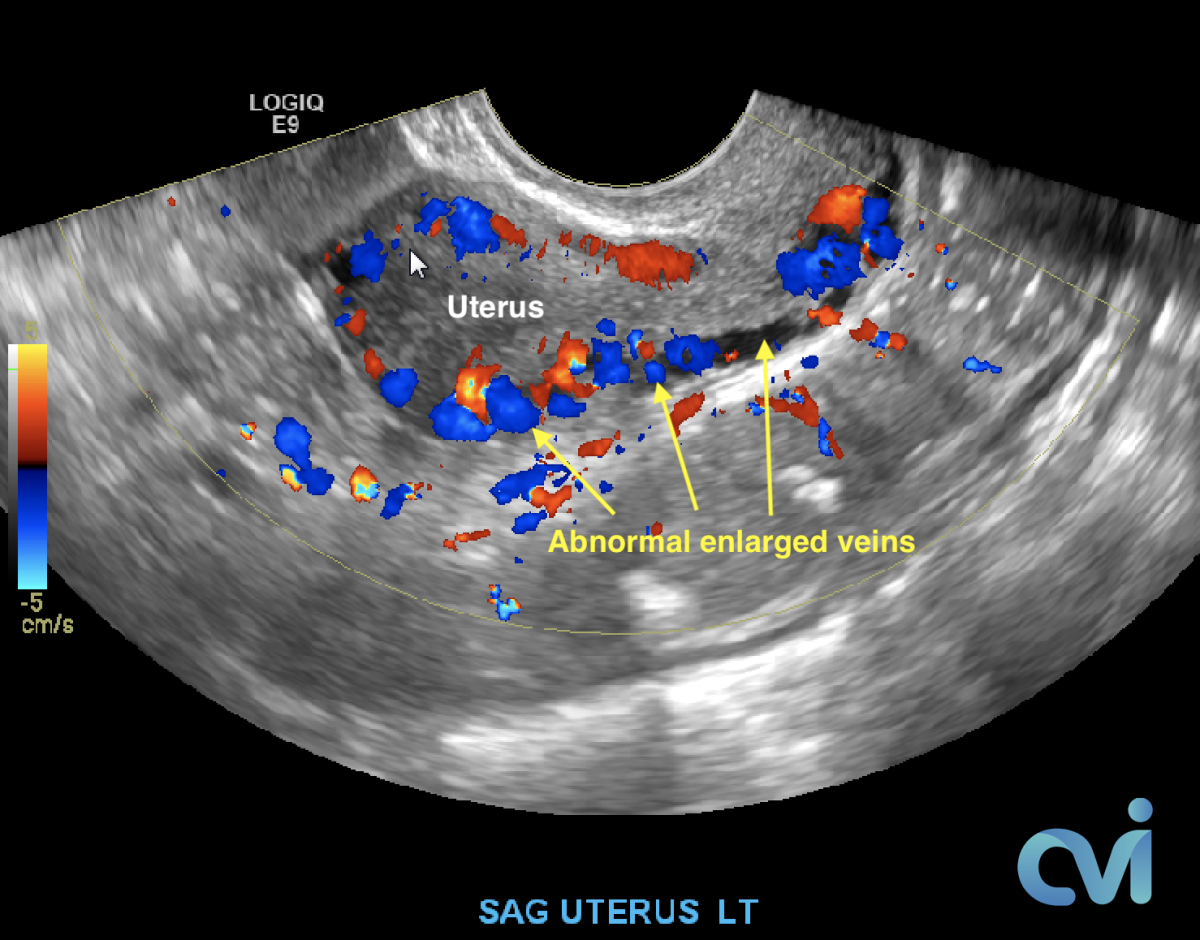

Pelvic Venous Congestion Syndrome

Pelvic Congestion Syndrome (PCS) or Pelvic Venous Congestion Syndrome (PVCS) is essentially varicose veins of the ovaries. Varicose veins are most commonly seen in the legs and are caused by the veins becoming less elastic resulting in abnormal flow of blood causing it to pool in certain areas, leading to enlarged painful veins. This is also what happens to the pelvic veins in pelvic congestion syndrome.

The abnormal veins dilate and cause varicose veins around the ovary and uterus because the valves don’t work properly. Blood flow is in the wrong direction, pooling in the veins and causing them to enlarge.

PCS can be diagnosed by Ultrasound or CT of the Abdomen and Pelvis.

Ultrasound examination is the least invasive study and can identify enlarged veins around the uterus and pelvis. However, sometimes the veins in the pelvis are difficult to see or can be missed if the technician is not specifically looking in the right area.